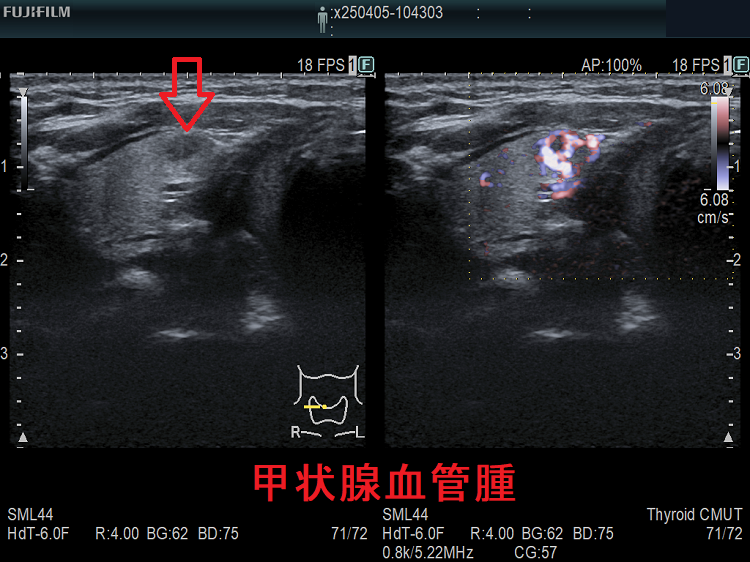

甲状腺血管腫(拡大) ドプラーモード(eFlow);腫瘍内血管が3次元的に見え、毛玉の様。